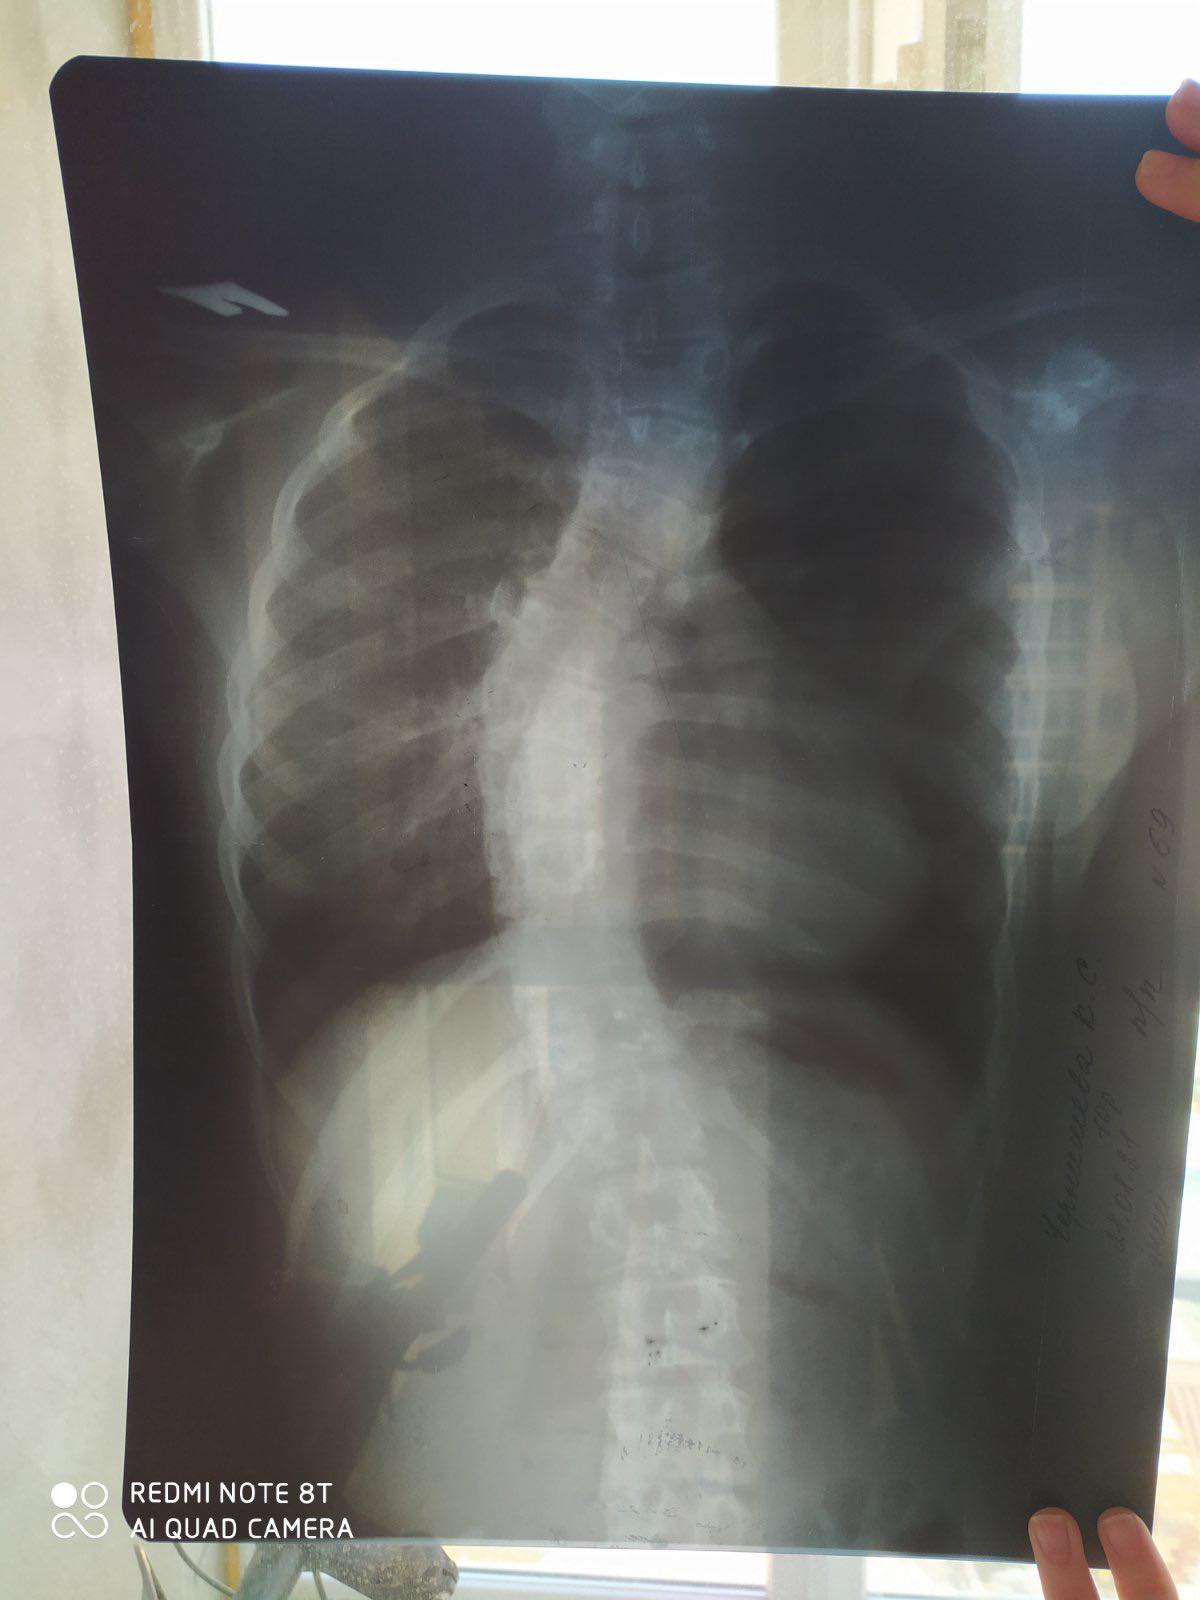

«Друзі, гайсинчани і не тільки, дуже вас прошу допомогти нам зібрати цю шалену суму в 220 500 грн на операцію моїй похресниці, потрібно оперувати спину, рівняти хребет. Я дуже прошу будь- якої допомоги, дівчинка кругла сирота, репости, інформаційні розповіді, може, хто має можливість фінансово підтримати.